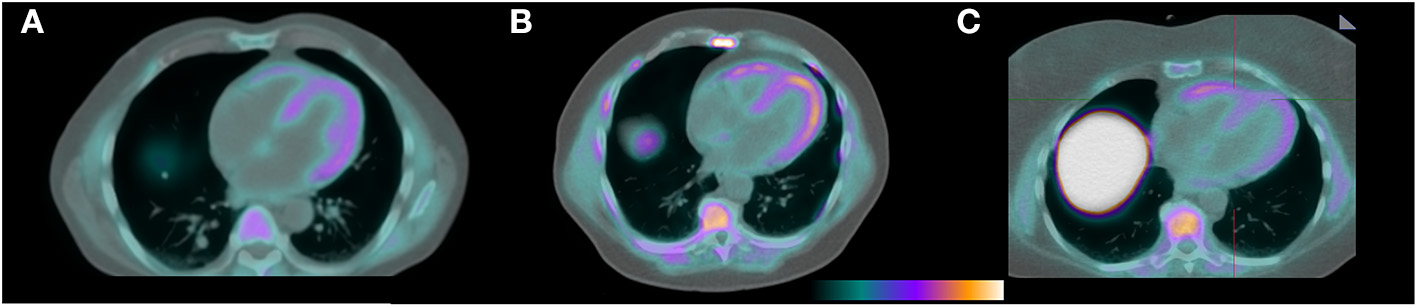

F18-florbetapir imaging showed visible radiotracer uptake in the myocardium in all patients (Figure 1) with mean SUV 2.3 ± 0.4. Patient 7 was asymptomatic from a cardiac perspective with normal levels of troponin T and NTproBNP, but had a positive PYP study (Table 1) in the setting of negative testing for a monoclonal protein and was considered to have cardiac amyloidosis at the time of enrollment. This patient had the highest myocardial SUV value of 3.3. Mean SUV for patients at risk was 2.3 ± 0.4, and for controls was 2.2 ± 0.3. All patients had myocardial SUV values above previously described healthy controls (SUV 1.4-1.7), and all patients had mean myocardial counts more than 2x blood pool counts (8). Blood pool, liver, and paraspinal muscle SUV values are also shown in the Table 1.

Figure 1

F18-florbetapir PET/CT images demonstrating identifiable myocardial uptake of radiotracer in the patient with confirmed cardiac amyloidosis by technetium PYP (A, mean myocardial SUV 3.3), a patient with light chain MGUS and a potential for having cardiac AL amyloidosis (B, mean myocardial SUV 2.7), and a control patient with a negative tenosynovial biopsy for amyloidosis at the time of carpal tunnel release surgery (C, mean myocardial SUV 2.0).